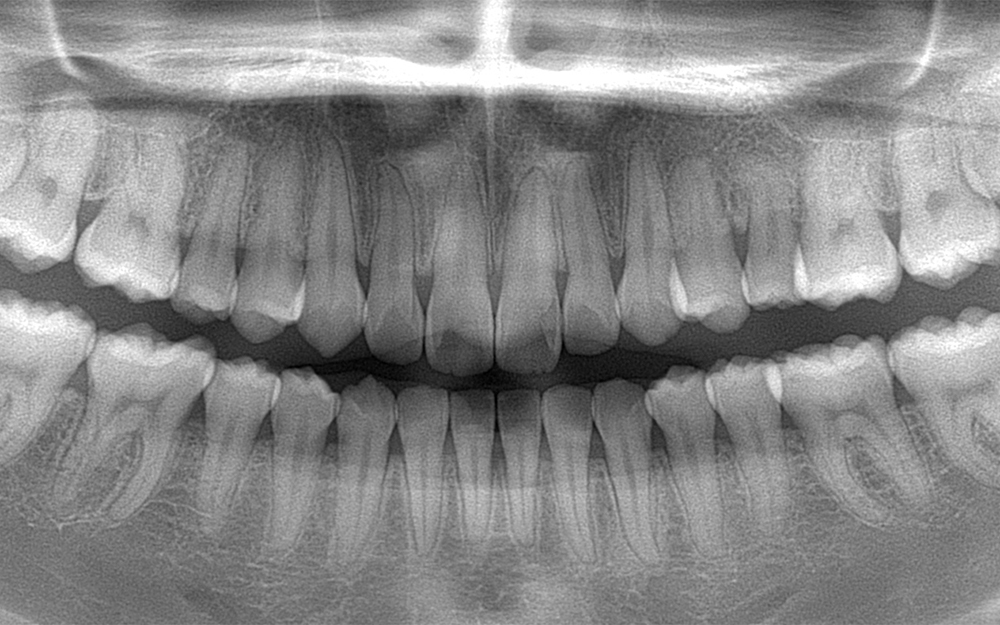

歯並びを治したいと来院。

ワイヤー矯正治療によって歯並びの改善を行った。

前歯の叢生の治療とともに左上乳歯の晩期残存と永久歯埋伏の治療も行った

乳歯を抜歯後、

埋伏している永久歯を牽引

矯正治療中と矯正治療終了後の

矯正治療中と矯正治療終了後のリテーナー。矯正治療終了後のCT